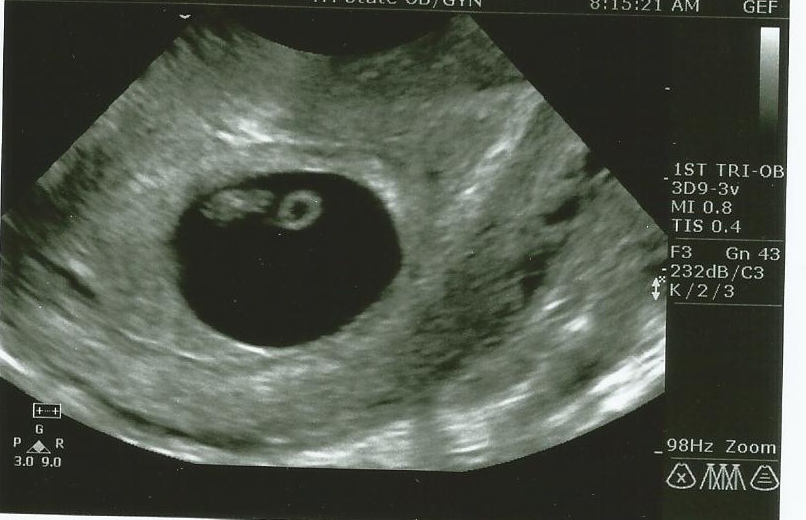

I will be having my 20 week ultrasound in a few weeks, and I was just looking at my ultrasound from 7 weeks, and thought I'd post it to get some Ramzi guesses. I don't put a lot of weight into the Ramzi theory, but it couldn't hurt to get some different opinions. Thanks in advance.Attachment 8609